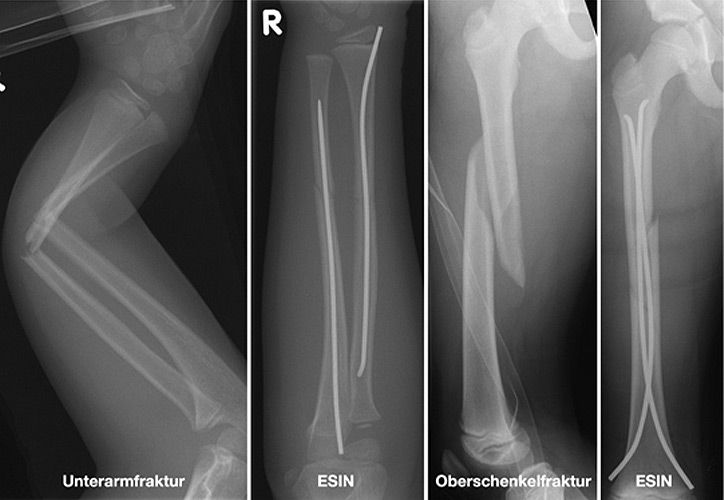

Einige Frakturen müssen auf Grund ihrer Achsabweichung operiert werden. In einer Narkose wird die Fraktur eingerichtet und ggf. mit Metall stabilisiert. Dazu stehen eine Reihe von Methoden (Osteosynthesen) zur Verfügung, die speziell für Kinder entwickelt wurden, um Wachstumsfugen zu schonen und nicht zu verletzen: Die ESIN (elastisch stabile intramedulläre Nagelung) hat sich als minimal invasives Standardverfahren zur Stabilisierung von Schaftfrakturen der großen Röhrenknochen (Unterarm, Oberarm, Unterschenkel, Oberschenkel) etabliert. Die Implantate können über winzige Schnitte eingebracht werden, eine gipsfreie Nachbehandlung ist ein weiterer entscheidender Vorteil.

Kirschner-Draht-Osteosynthese

Andere Verfahren der operativen Frakturversorgung im Kindesalter sind die Kirschner-Draht-Osteosynthese, die Verschraubung, der Fixateur und die Plattenosteosynthese. Metallentfernungen werden ambulant durchgeführt, Nachuntersuchungen zum Ausschluss etwaiger Wachstumsstörungen erfolgen in unserer Frakturensprechstunde.